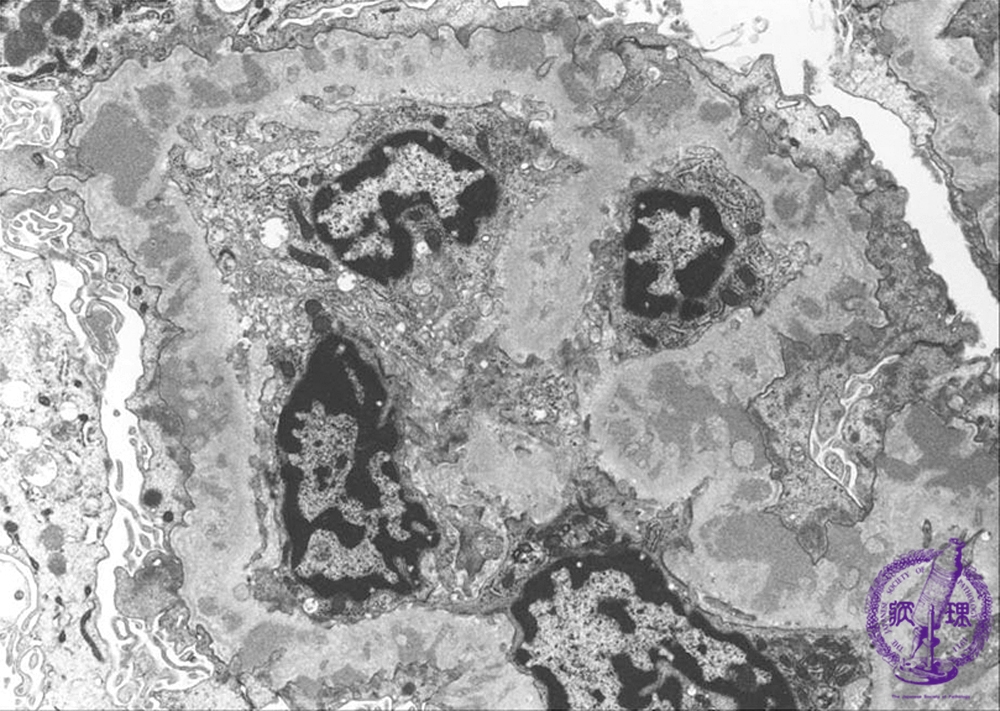

- ★(2)Membranous nephropathy

Electron microscopic findings, stage III: The electron dense subepithelial deposits (red arrow) are completely enveloped by thickened basement membrane (blue arrow).